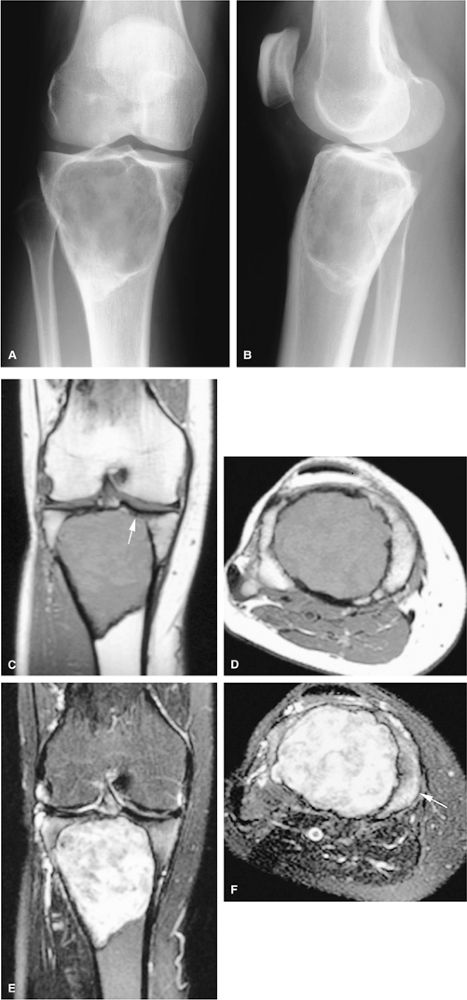

![]() |

FIGURE 14-64 ● Giant cell tumor. (A) Anteroposterior and (B) lateral radiographs show an osteolytic lesion involving the subchondral bone of the tibial plateau. Cortical thinning and expansion can be seen. (C) Coronal T1-weighted image shows subchondral extension of the tumor (arrow). Tumor contents demonstrate low signal intensity on the coronal (C) and axial (D) T1-weighted images and are hyperintense on the coronal (E) and axial (F) T2-weighted images. Peritumoral edema (arrow) is noted on the axial fat-suppressed T2-weighted fast spin-echo image (F).